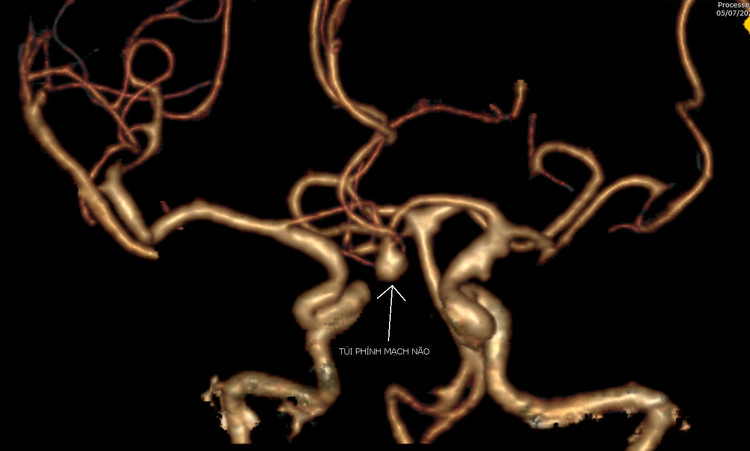

Qua kết quả chụp cắt lớp vi tính, các bác sĩ phát hiện hình ảnh chảy máu khoang dưới nhện do vỡ phình động mạch não thông trước, kích thước túi phình 5x6mm.

Hình ảnh túi phình mạch não của bệnh nhân Th. qua phim chụp cắt lớp vi tính dựng hình mạch não 3D |

Hình ảnh túi phình mạch não của bệnh nhân Th. qua phim chụp cắt lớp vi tính dựng hình mạch não 3D